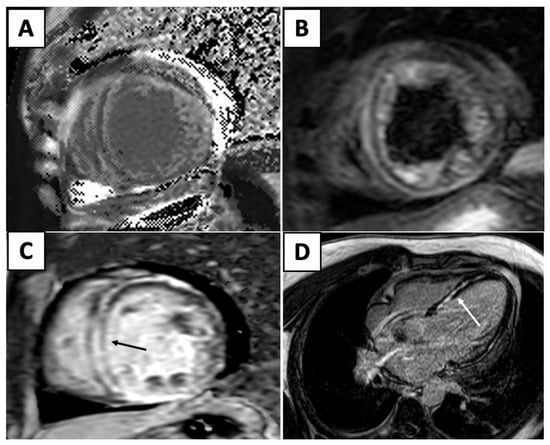

| Imaging Modality | Imaging Illustrations | Description |

|---|---|---|

| Echocardiography | ![]() | Mild left-ventricular dilation and systolic dysfunction |

| Cardiac MRI | ![]() | Short-axis view reveal interventricular mid-myocardial LGE (black arrow). |